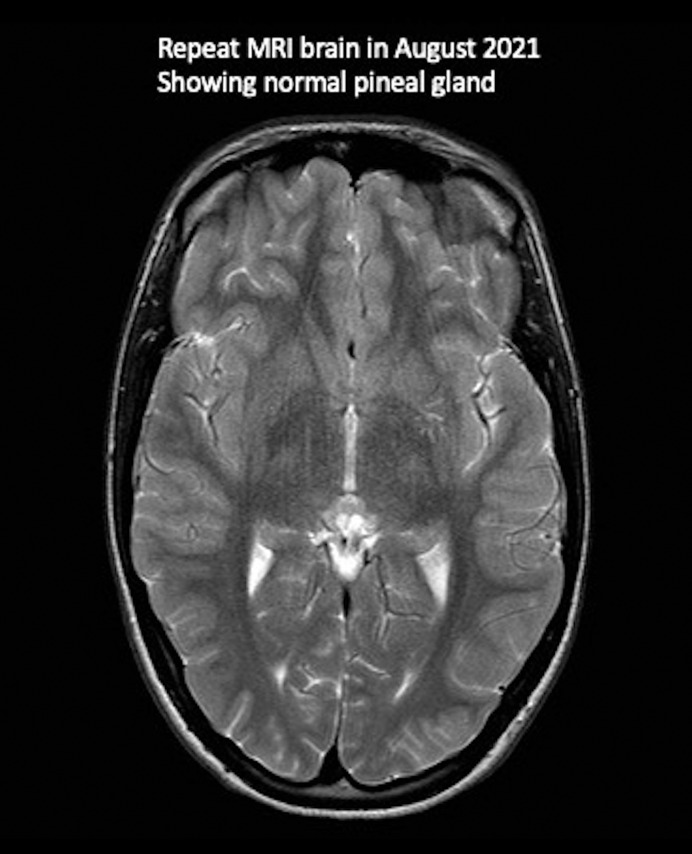

Case report: An 11-year-old female, diagnosed with migraine with an aura and PC, was benefitted by individualized classical homeopathic therapy using the homeopathic preparation Phosphorous and Natrum muriaticum. The symptoms of migraine improved, and the incidentally diagnosed PC completely resolved during the course of treatment.